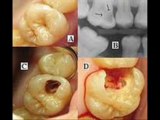

Dentin (American English) or dentine (UK English)(Latin: substantia eburnea) is a calcified tissue of the body, and along with enamel, cementum, and pulp is one of the four major components of teeth. It is usuallly covered by enamel on the crown and cementum on the root and surrounds the entire pulp. By weight, 70% of dentin consists of the mineral hydroxylapatite, 20% is organic material, and 10% is water.[1] Yellow in appearance, it greatly affects the color of a tooth due to the translucency of enamel. Dentin, which is less mineralized and less brittle than enamel, is necessary for the support of enamel.[2] Dentin rates approximately 3 on the Mohs scale of mineral hardness.[3]